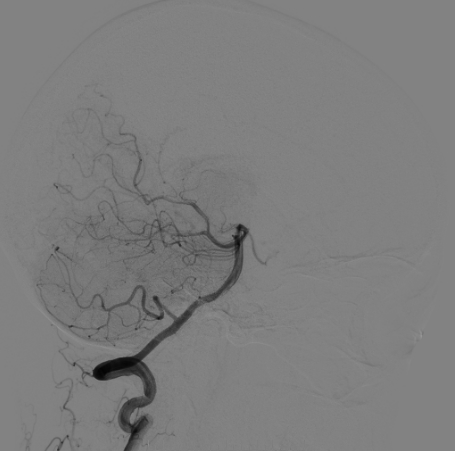

脑血管造影

右侧颈总造影:右侧大脑中动脉瘤

右侧大脑中动脉瘤,瘤颈处发出颞支,颈宽3.79mm,瘤高3.51mm,远近端载瘤动脉直径分别为2.43mm、2.52mm。